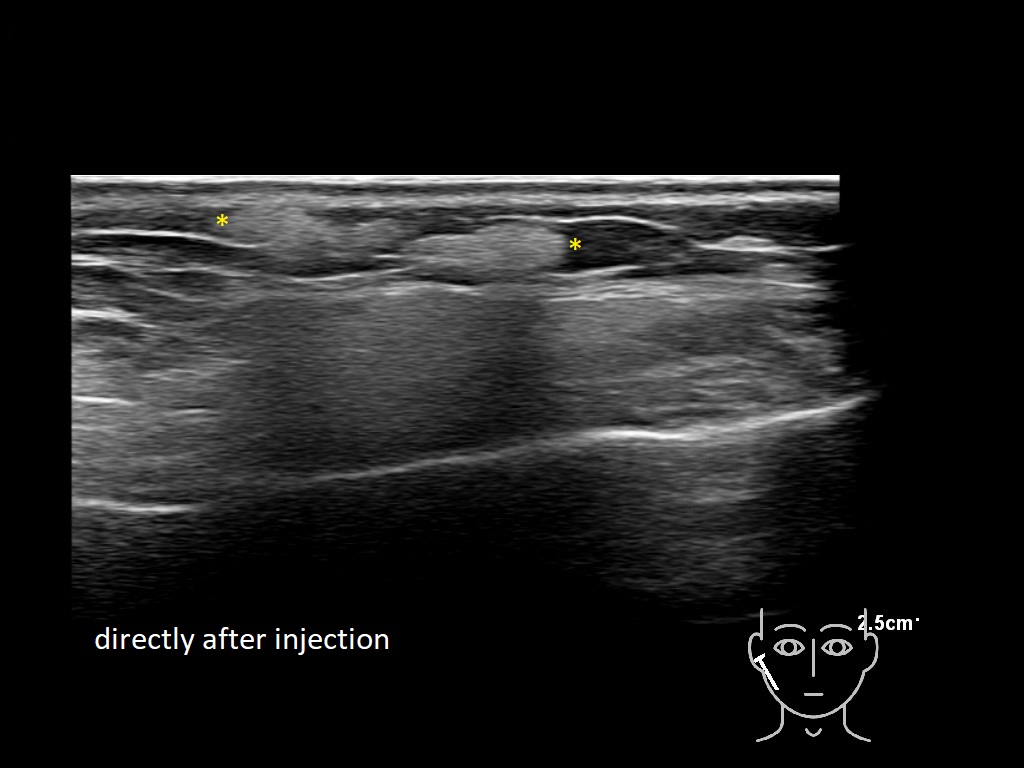

Fillers

Draw in the image on the right where the fillers are located. To check if your answer is correct, please click on the secondary image.

Fillers

Draw in the second image below where the fillers are located. To check if your answer is correct, swipe the first image to the right.